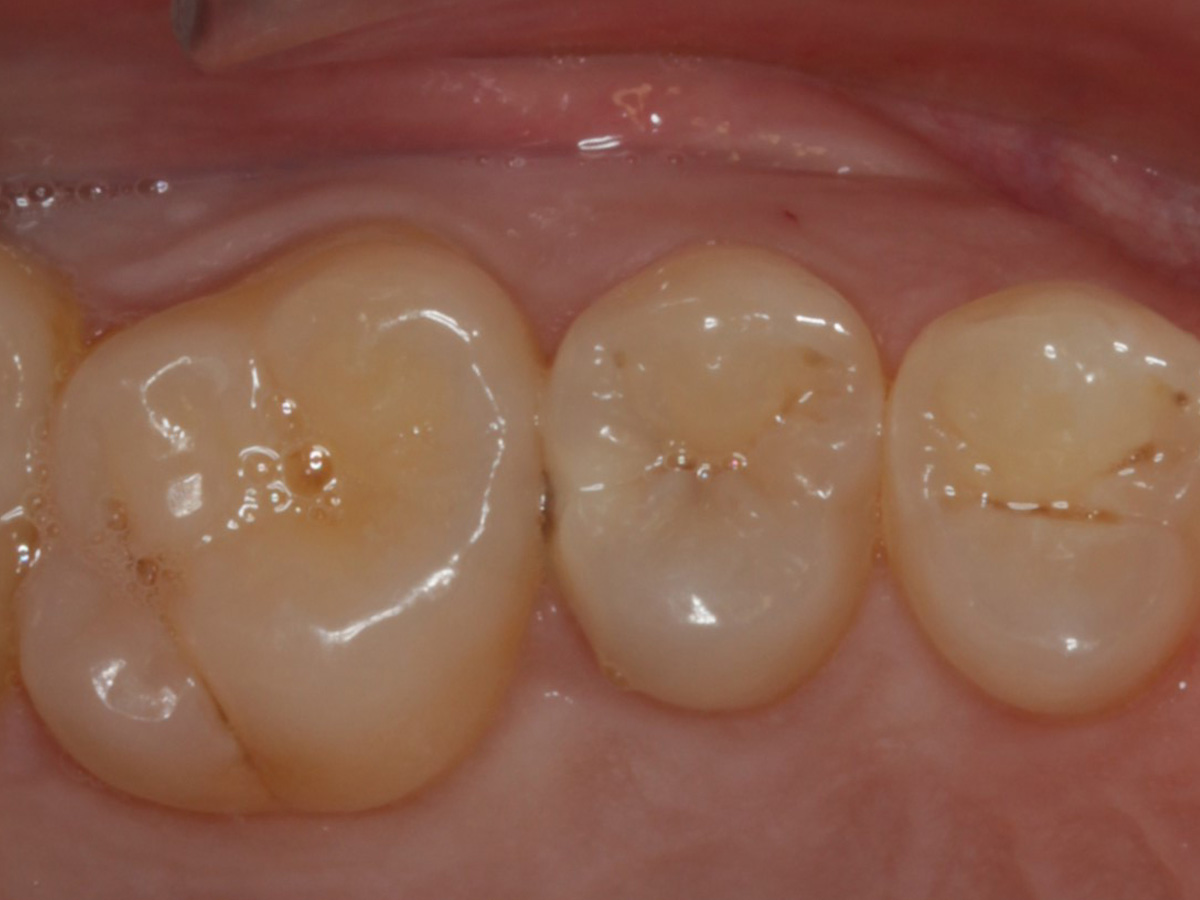

Abbildung 18

Fertige Restauration

Abbildung 19

Röntgenkontrolle: approximal fast auf Knochenniveau endender spaltfreier Füllungsrand dank interproximaler tieferer Verlängerung der Evolve Matrize